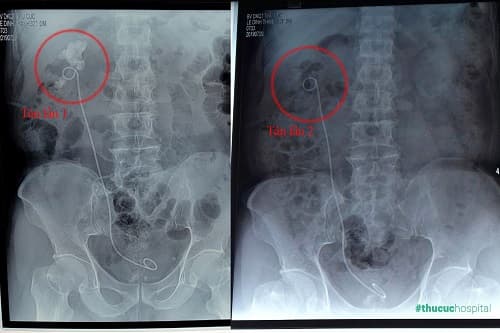

Hình ảnh khối sỏi “khổng lồ” 7cm trong thận phải của bệnh nhân L.Đ.Thanh (62 tuổi, Hà Nội).

Bệnh nhân L.Đ.Thanh (62 tuổi) tìm đến Bệnh viện Đa khoa Quốc tế Thu Cúc với tình trạng rất phức tạp. Phim chụp CT cho thấy thận tráiphải có sỏi to, kích thước 7 cm, sỏi phân nhánh, lấp kín các đài bể thận. Bác sĩ CKII Phạm Huy Huyên (Phó Giám đốc – Trưởng khoa Ngoại của Bệnh viện Thu Cúc) xác định đây là loại sỏi san hô rất hiếm gặp, đặc biệt kích thước rất lớn. Bình thường sỏi thận khoảng 2cm đã được xếp vào loại to nhưng sỏi của bệnh nhân Thanh lớn hơn gần nhiều lần. Tiền sử 2 lần mổ lấy sỏi cũng là vấn đề đáng lo ngại. Nếu tiếp tục mổ mở để lấy sỏi như trước đây, người bệnh có nguy cơ gặp phải nhiều biến chứng nguy hiểm, chưa kể vết mổ dính cũng sẽ gây khó khăn cho bác sĩ trong quá trình phẫu thuật. Tuy nhiên nếu không điều trị sỏi sẽ tàn phá các nhu mô thận, làm mất chức năng thận, có thể phải cắt thận.